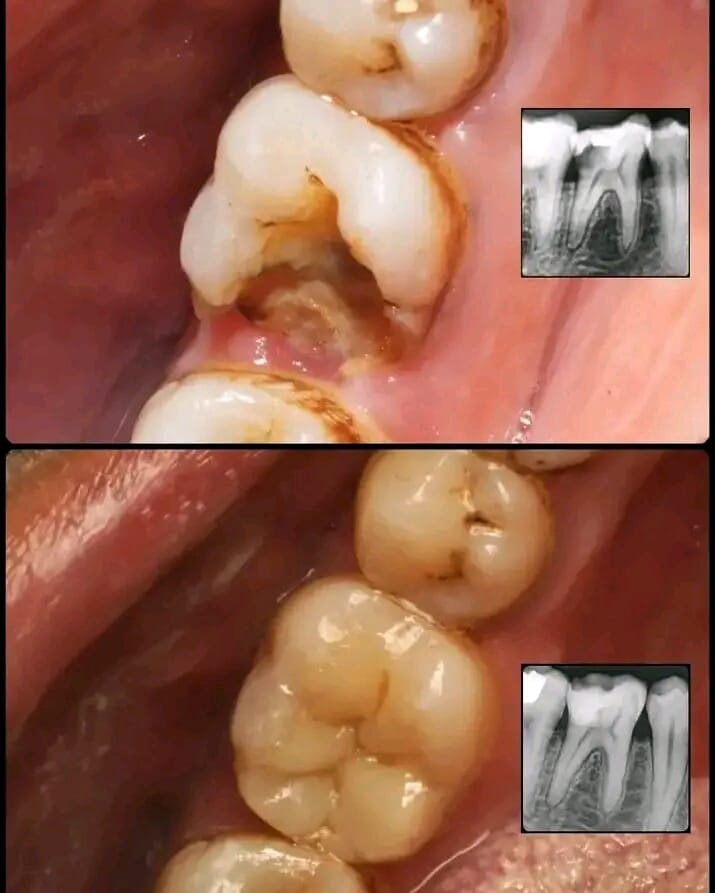

Dental Crowns and Bridges

General Dentistry (Check-ups, Cleanings, Fillings)